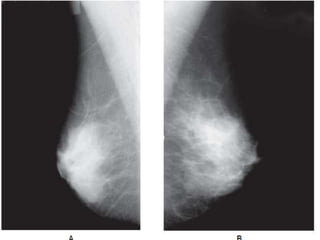

CRANIO-CAUDAL VIEW

 The casette is placed under the

breast at the level of the

inframammary fold .

 The breast is then pulled until the

inframammary fold is taut .

 Compression is applied and Xray

beam is directed vertically from

above .

 Postero medial aspect should also

be included .